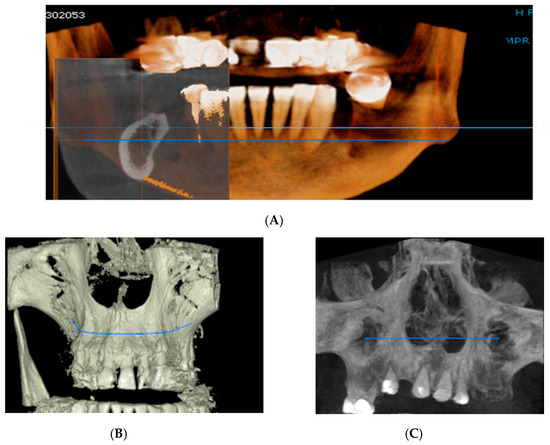

For image acquisition, we used a ProMax 3D CBCT unit (Planmeca, Helsinki, Finland), with the previously mentioned settings. Images were acquired and saved in JPEG format. To locate implant target sites, bone density, and to record the mean CT number of the trabecular bone from these sites, we used the OnDemand 3Ddata App™ software (Cybermed Inc., Seoul, South Korea). In each site, our region of interest was a square volume of bone located within the alveolar ridge (Figure 3, Figure 4 and Figure 5). All data recorded were input into the Microsoft Office Excel™, 2017 version, analysis software (Microsoft, Redmond, WA, USA).

Figure 3.

CBCT images used in the study, showing sagittal sections of bone.

Figure 4.

CBCT images used in the study showing the density of bone.

Figure 5.

Image showing the bone density measured in Hounsfield units (HU) as well as the standard deviations of the volume.

Each voxel of the CBCT volume is characterized by a CT number, expressed in HU (Hounsfield Units). The software displays the mean value of the CT numbers of the constituent voxels and the standard deviation of these CT numbers (Figure 5).